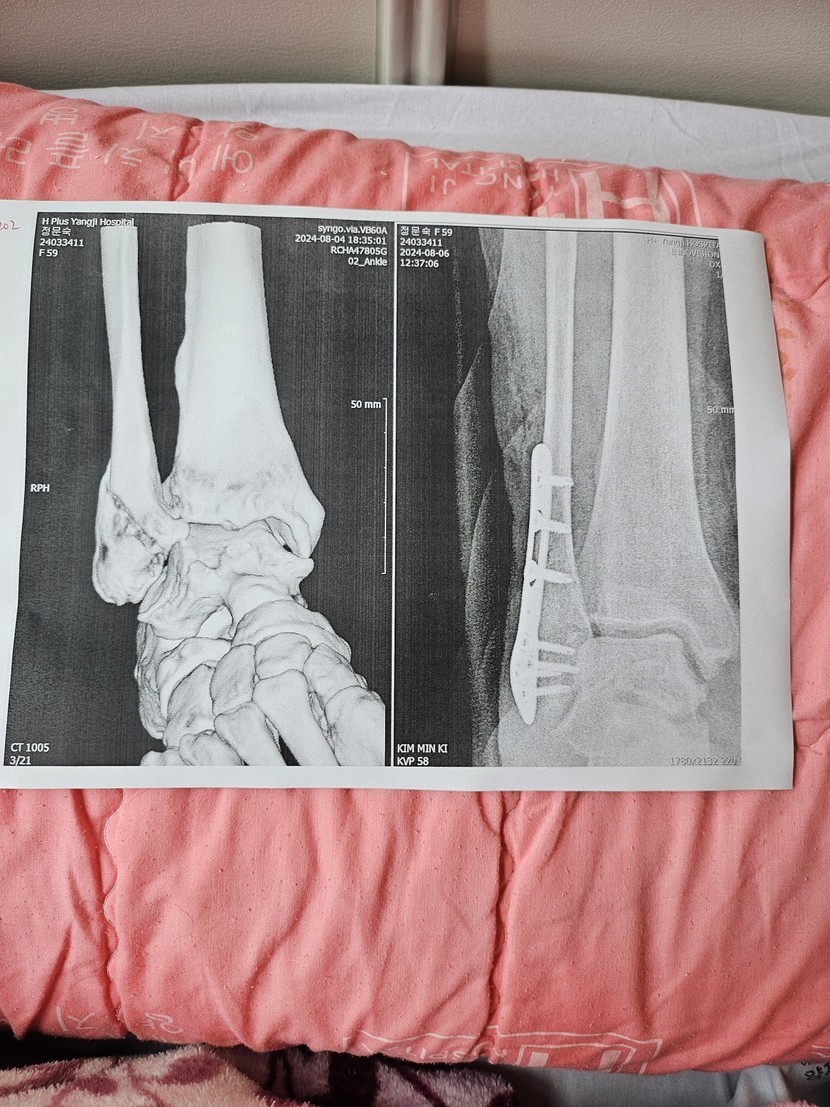

병원에서 휴가를 ㅜㅜ

더 튼튼해지길 기도하면서~~~